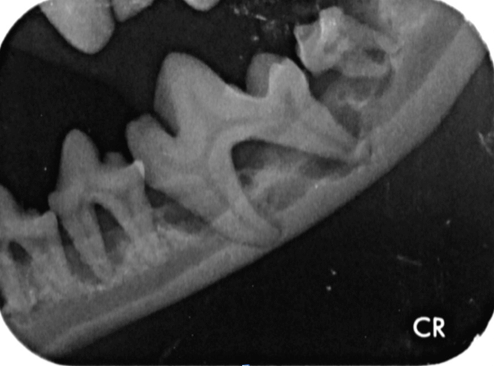

Weil wir von außen also nur einen Bruchteil des Zahns sehen können und schon gar nicht das Innenleben oder den Kiefer beurteilen können, ist das Zahnröntgen unerlässlich. Aber auch eine gute Sondierung des Zahnes und seines Gingivasulcus ist sehr wichtig, um Attachmentverluste und Furkationen im Zwischenwurzelbereich festzustellen. Dabei sollte jeder Zahn an mindestens vier Stellen sondiert werden (Abb. 6).

Zahnschmerzen werden leider oftmals unterschätzt. Der einzige Weg, um schmerzhafte Prozesse im Bereich der Zahnwurzeln zu erkennen, ist das dentale Röntgen und eine gründliche Aufnahme des gesamten Zahnstatus. Daher gehören zu jeder professionellen Zahnsanierung auch Röntgenaufnahmen aller Zähne mit ihren Wurzeln und die Sondierung aller Zähne an mindestens vier Stellen."

In Narkose sah man auf Leilas Röntgenbildern dann das gesamte Ausmaß ihrer Zahnerkrankung. Bis auf die Canini wiesen alle Zähne hochgradige Wurzelentzündungen mit Osteolysen des Kieferknochens auf. Deshalb konnte man auch schon von außen die Zahnhälse freiliegend sehen. Im Wurzelbereich waren die Veränderungen so schlimm, dass der Unterkiefer kurz vor einer Fraktur stand.

Es ist sehr wichtig zu verstehen, dass eine Zahnreinigung ohne Aufnahme eines kompletten Zahnstatus inklusive Zahnröntgen nichts weiter ist als eine kosmetische Behandlung, da krankhafte Prozesse übersehen werden (abb. 7-10).